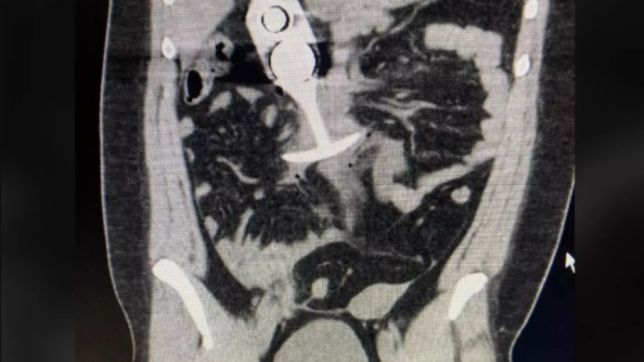

De acordo com relatos, o brinquedo subiu para a cavidade torácica da paciente “na velocidade da luz,” mas ela foi sortuda o suficiente em não ter danos extensos. Mesmo assim, no relatório, o médico disse que a mulher não parava de gritar.

Uma foto do brinquedo no exame circulou online e assustou muita gente. No Twitter, alguém até brincou: “Melhor nunca usar um butt plug pra fazer exame.”